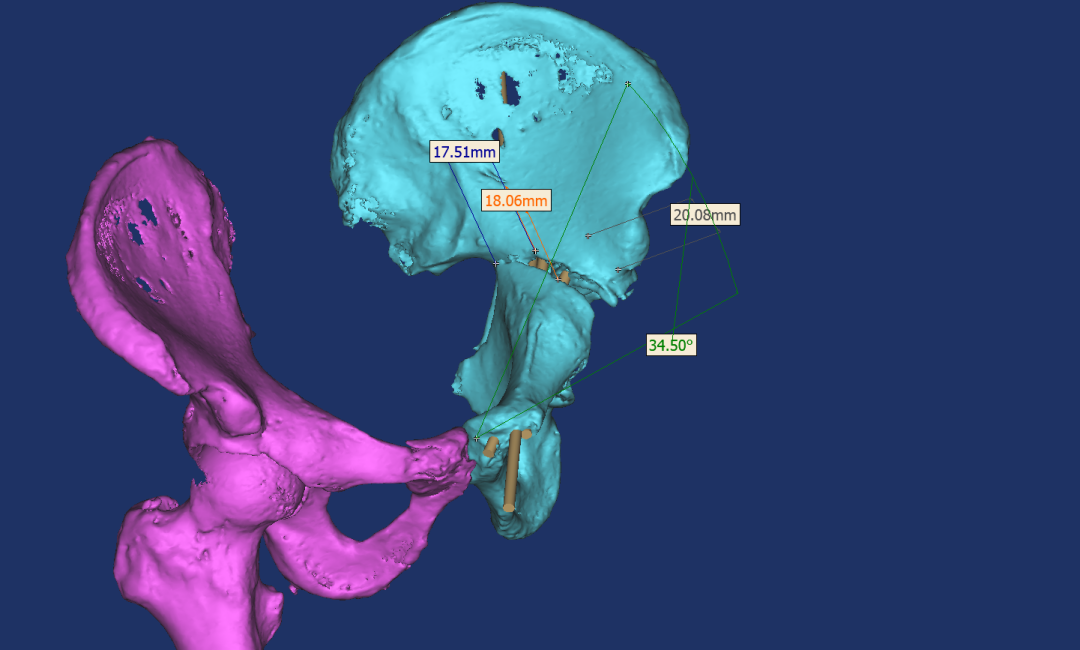

张洪彬医生对患者骨盆三维CT进行了术前虚拟仿真,辅助术者规划骨折复位过程及通道螺钉的置入长度、角度及方向。在患者伤后2周内,由刘利主任主刀,采取单一Kocher-Langenbeck 入路手术入路,术中仔细对坐骨神经及旋股内侧动脉进行了保护,降低了远期发生神经损伤及股骨头缺血性坏死发生风险,完成复位后,应用两块重建钢板及一枚通道螺钉就完成了复杂骨折的固定。术后复查DR及CT骨折复位理想,内固定位置满意,没有发生螺钉进入关节腔的情况。患者得到了早期功能康复锻炼的有利条件。患者现已顺利出院。